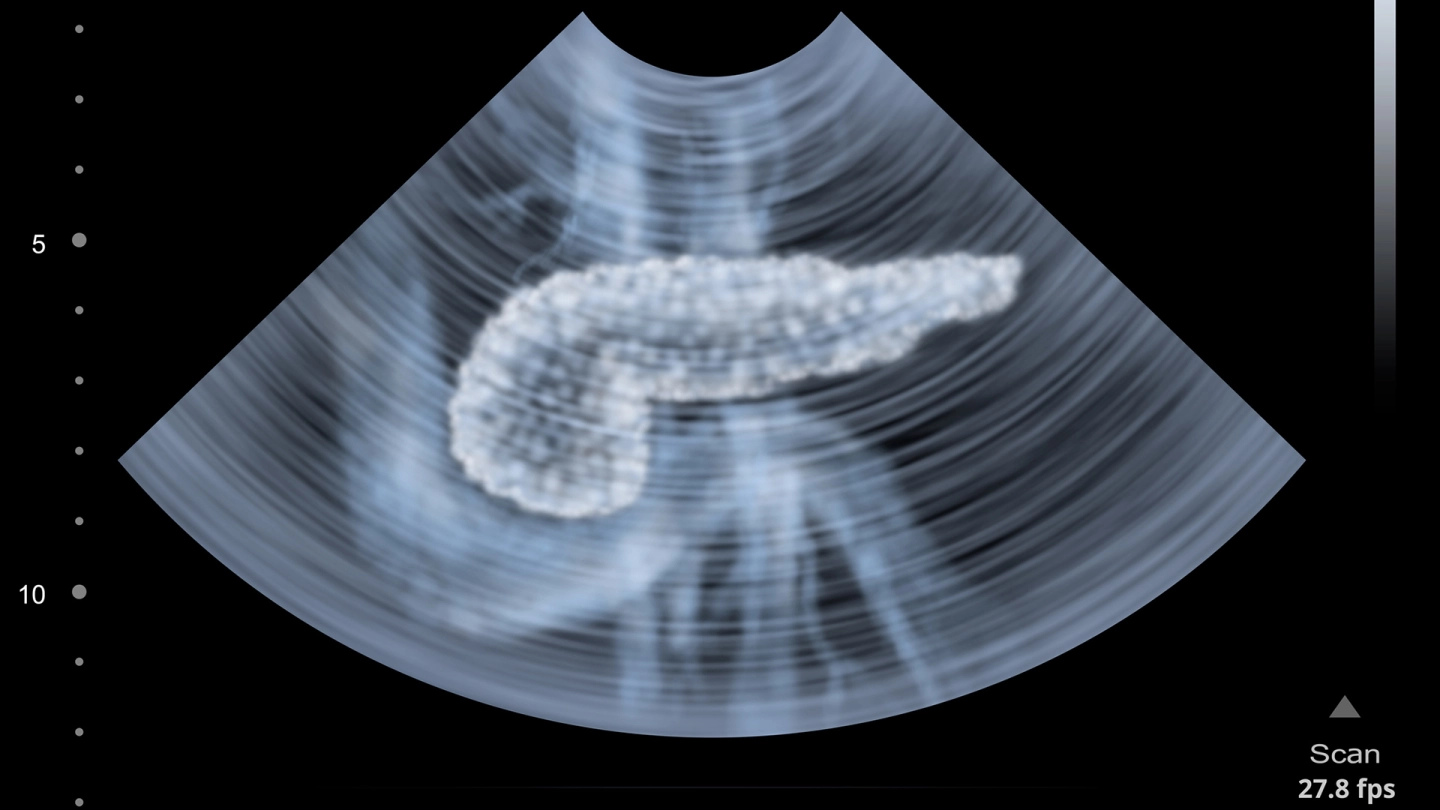

Die Bauchspeicheldrüse (Pankreas) liegt hinter dem Magen zwischen der Milz und dem Zwölffingerdarm. Sie lässt sich in drei Abschnitte einteilen: den Kopf, den Körper und den Schwanz.

Bei Verdacht auf Bauchspeicheldrüsenkrebs können Ärzte mit verschiedenen bildgebenden Verfahren die Diagnose weiter erhärten. Mögliche Untersuchungsverfahren sind:

- ein Ultraschall des Oberbauches (Sonographie) durch die Bauchdecke,

- ein Ultraschall von innen (Endo-Sonographie),